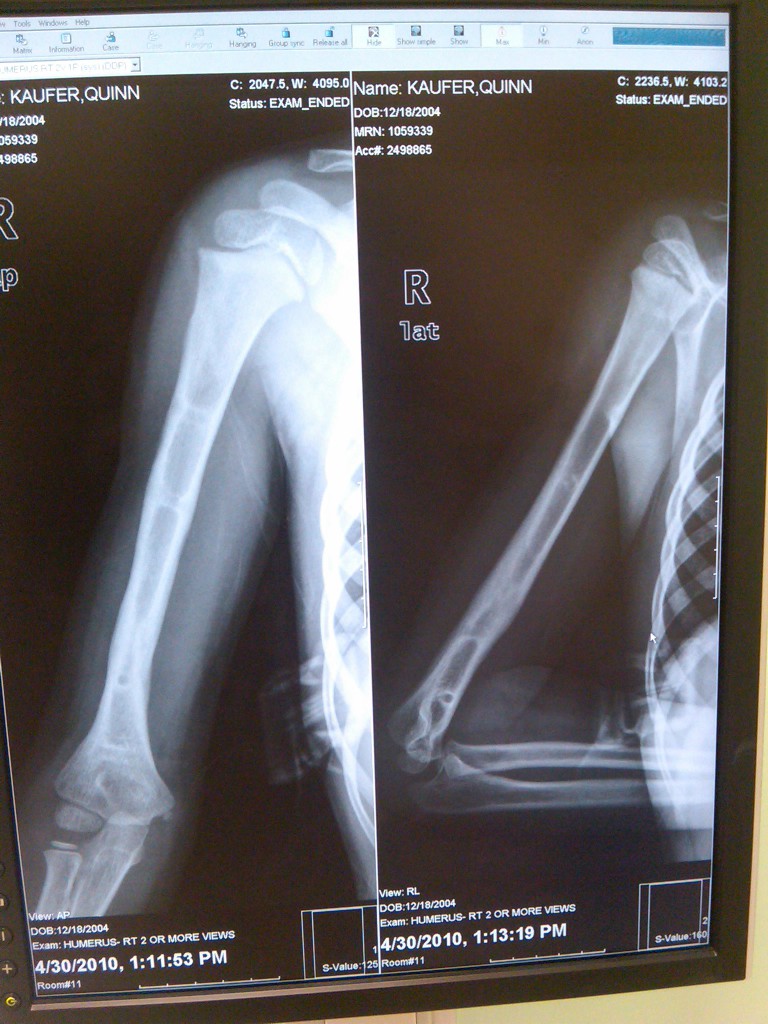

When our son Quinn was four years old, we called Dr. Scher's office to describe his acute condition. It was Saturday of Columbus Day weekend, he was sick and injured and we urgently begged for someone at HSS to take over his care. As a patient, Quinn was completely unknown to the HSS staff. Despite that, the HSS team listened to us and believed that Quinn was unnecessarily suffering after a severe open fracture to his humerus had left him hospitalized for a week with unresolved symptoms, extreme pain and intermittent listlessness. Our situation sounded complicated: possibly surgically resetting a break, excessive infection, and other unknowns.

It would have been easier for HSS to leave him with the doctors who were first caring for him. However, Dr. Scher took on our case and we transported Quinn to the city. There, the staff provided a new perspective on his injury, team work among doctors Dr, Scher, Dr. Widmann and Dr. Hotchkiss performed the first surgery together with extraordinary long term medical and therapeutic care. It is not an exaggeration to say that Drs. Scher, Widmann and Hotchkiss saved his arm and possibly his life.

Due to poor initial attention, alarming aspects of Quinn's condition had been overlooked. For ten days, his body had been suffering from foreign body infection due to playground wood chips that were lodge in his arm from the original accident. He also had undiagnosed nerve damage that had destroyed all sensation in his arm and hand. After five surgeries and extensive rehabilitation at HSS, Quinn is not only a rock start in the classroom but also an actual rock climber on a local team. He still speaks of  his doctors, knowing that their expertise and compassion gifted him full use of his hand and arm.